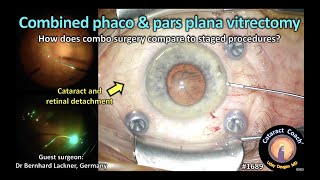

Phaco - Vitrectomy for Combine Retina Detachment from severe PSCR CataractCoach™ 1689: combined phaco and pars plana vitrectomy

CataractCoach™ 1689: combined phaco and pars plana vitrectomy Combined phaco-vitrectomy for R+T RD

Phaco - Vitrectomy for Combine Retina Detachment from severe PSCR CataractCoach™ 1689: combined phaco and pars plana vitrectomy

CataractCoach™ 1689: combined phaco and pars plana vitrectomy Combined phaco-vitrectomy for R+T RD